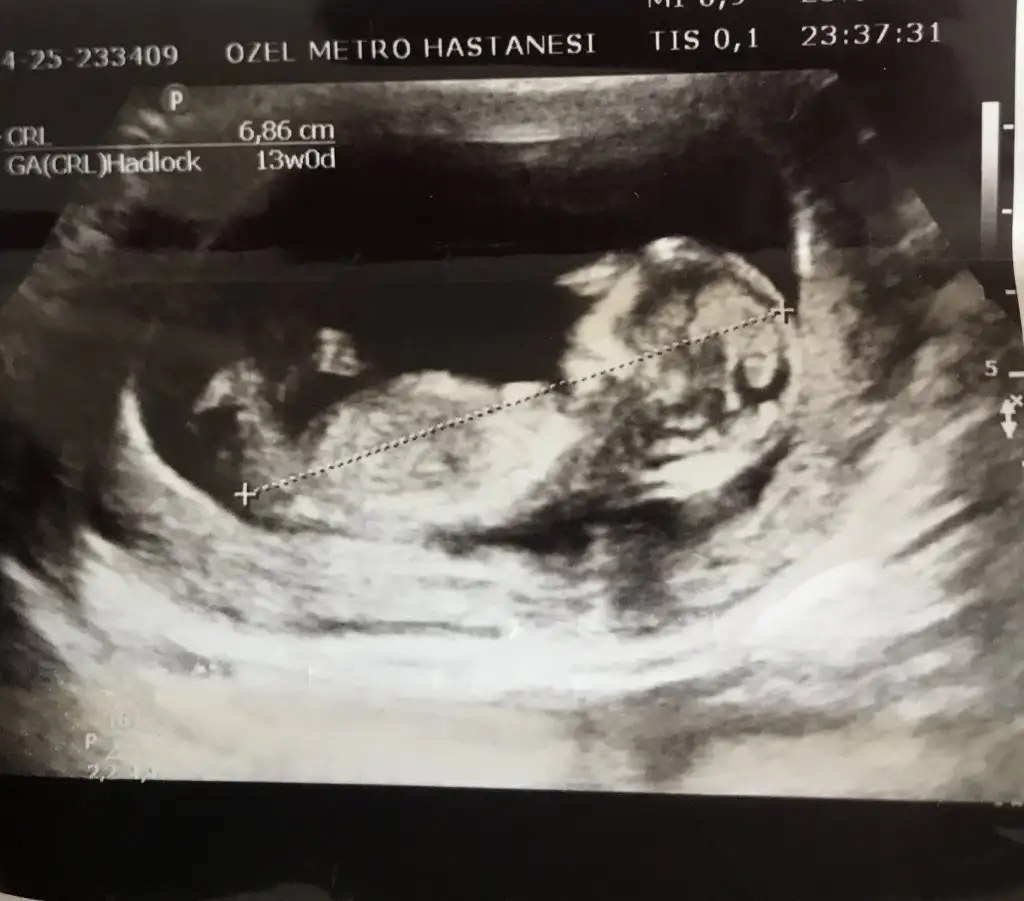

prenses gibiPasha22 merhaba;

Rica etsem benim bebişiminde cinsiyet tahminini yapabilir misiniz?

9+1 karından ultrason ile çekildi. Çok teşekkür ederim. Sevgiler.